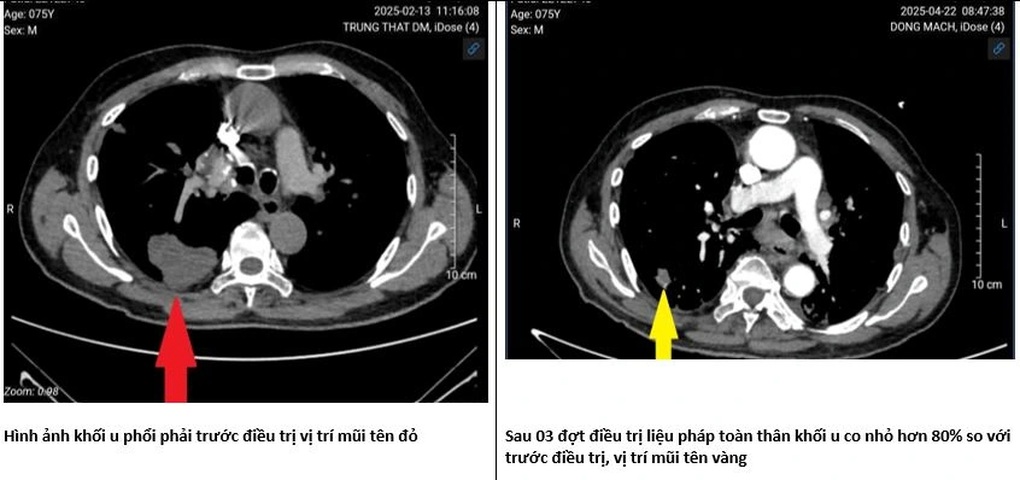

Denna expert delade med sig av ett fall med en 75-årig patient som hade haft lungcancer i 3 år.

Patienten hade genomgått en operation för att ta bort lobulen som innehöll tumören, men sjukdomen återkom i slutet av 2024.

”När han kom tillbaka satt tumören inte bara i lungorna utan hade även spridit sig till lymfkörtlarna i halsen. Han gick ner i vikt, förlorade rösten, hade svårt att svälja, hade mycket ont och var tvungen att använda syrgas nästan hela dagen”, berättade Dr. Duy Anh.

Signifikant förändring av tumörstorlek efter behandling (Foto: Tillhandahållet av läkare).

Patienten behandlades initialt med en kombination av mindre toxisk kemoterapi och immunterapi.

Efter den första cykeln hade patienten mindre smärta, mindre andnöd och inga signifikanta biverkningar.

Vid den fjärde cykeln kan patienten prata, behöver inte syre, äter bättre och är särskilt mer aktiv.

”Efter 3 behandlingar försvann tumören i höger lunga; tumören i vänster lunga och tumörerna i lungbasen krympte med 50 % jämfört med före behandlingen; de supraklavikulära lymfkörtlarna krympte från 5 x 6 cm till 4,5 x 3,5 cm; vissa tumörer krympte till och med med 80 % jämfört med före behandlingen”, delade Dr. Duy Anh.